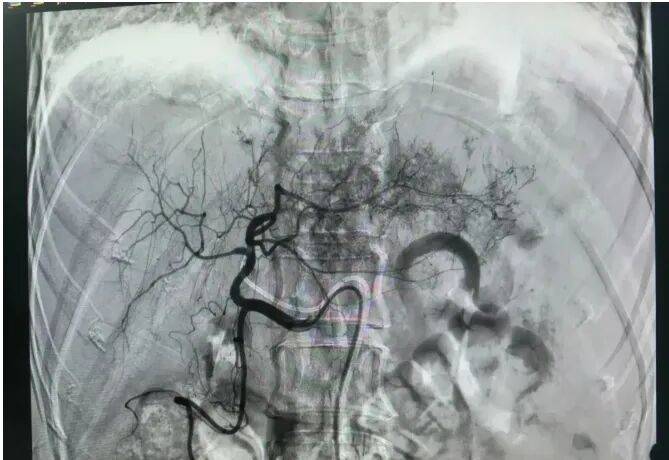

术后影像图

诊断明确后,我立即安排手术。我给这个患者做了股动脉穿刺,对肝癌破裂出血的责任血管进行选择性栓塞治疗。造影显示出血停止。另外,这样阻断肿瘤的供血,还有“饿死”肝癌细胞的作用。患者转危为安。(作者供职于河南省人民医院)